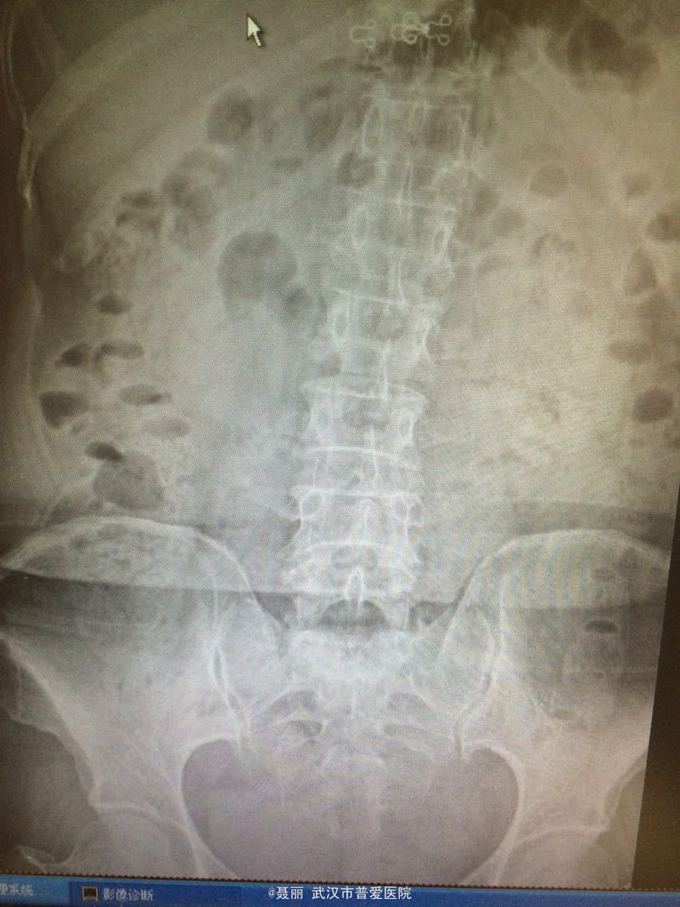

患者,女,61岁 因腰部疼痛,伴左下肢酸胀、疼痛、麻木5月余入院。 患者约5月前无明显外伤等诱因感腰腿疼痛不适,以腰部及左下肢为主,活动后左下肢疼痛加重,休息可缓解。 既往病史:既往体健,否认高血压、糖尿病等其他传染病史,否认食物药物过敏史。

辅助检查:2015年2月27号到我院拍腰椎MRI检查提示:L4椎体Ⅰ-Ⅱ度滑脱,腰椎退变。

初步诊断:腰椎滑脱症 治疗计划:1、完善相关检查:胸片、心电图,血常规,尿常规,肝肾功能电解质、术前全套 2,活血化瘀扩管治疗。卧床休息。 L4滑脱复位+L4/5椎间盘摘除、椎管减压+椎间cage3植骨融合术